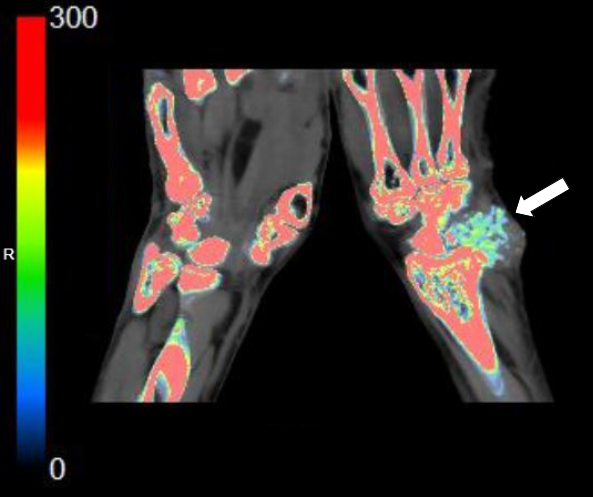

与X线平片及单能量CT相比,双能量能谱CT能够超早期显示更细小的尿酸盐结晶的存在;与MRI相比,双能量能谱CT可以进行多关节的扫描成像,不仅能够直观分析检查部位是否有尿酸盐结晶存在, 并且可以分析其数量、大小、形态、位置、分布以及临近关节骨质及软组织损害的情况。

腕关节尿酸盐(痛风石)沉积